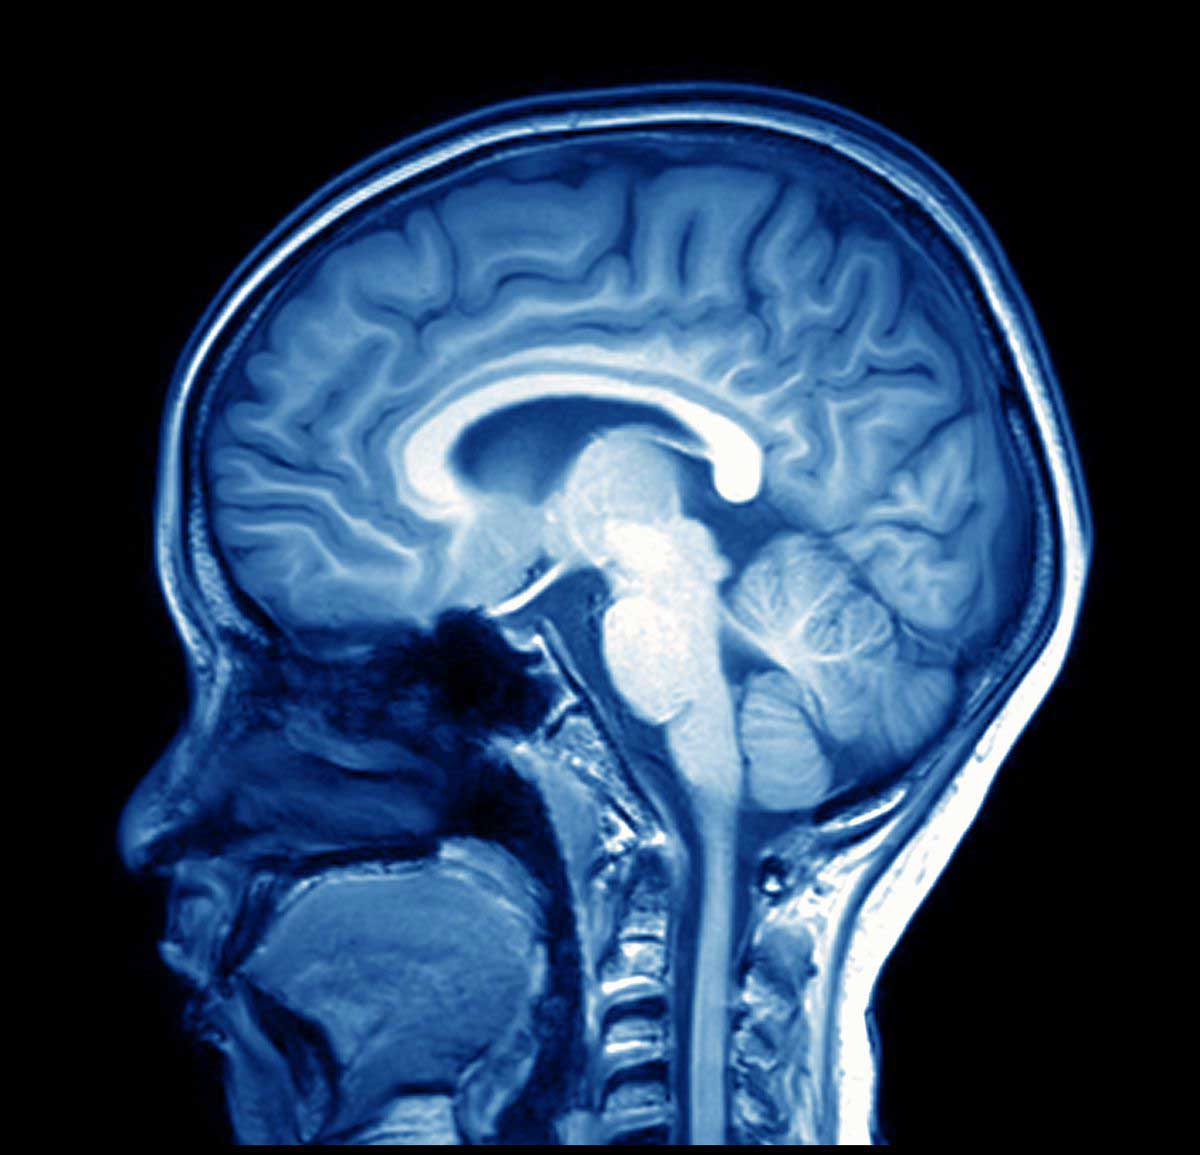

Brain-scan - Neuro-Laser Foundation

www.tbi.care

www.tbi.care

brain scan ptsd imaging medical research now doctors injuries differentiate traumatic between shows help neuro tbi

MRI Scan Image Of Brain | Regional Medical Imaging

www.rmipc.net

www.rmipc.net

brain mri imaging

ESA - MRI Brain Scan

www.esa.int

www.esa.int

mri brain scan alzheimer using space imaging human software scans wikipedia identifying esa researchers hypothalamus applications pillars medical wiki thalamus